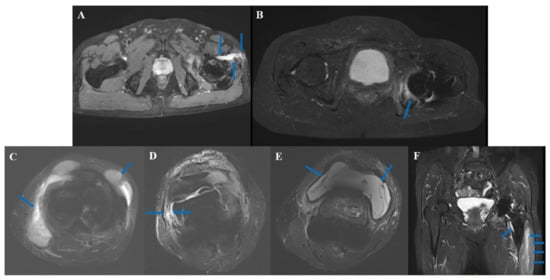

3.5. Typical Cases